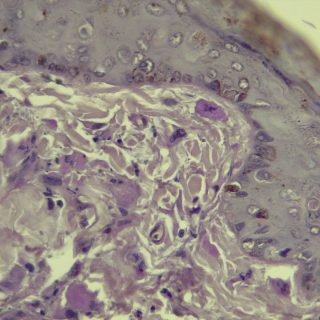

A vírus a csípést követően a bőrben elszaporodik, majd bekerül a véráramba, és a belső szervekben egy ismételt szaporodás után végül újra a bőrbe jut. Itt kialakulnak a klasszikus elváltozások, amelyek lényegében göbképződéssel járó gyulladásnak felelnek meg. A kórokozó hatására az irharétegben kialakulnak az ún. myxomasejtek (a myxomasejtek a mesenchyma-sejtekből kialakuló, nagy, sokszor nyúlványokkal rendelkező, módosult sejtek, amelyek tipikusak a myxomatosisban elhullott állatok irha rétegében) is. Az eddigi megfigyeléseink szerint a göbök a legintenzívebben a szemhéjakon, a száj körüli bőrképletekben és a genitáliákban jelennek meg, amelyet súlyosfokú vizenyő is kísér. Szövődményként gennyes jellegű orrgyulladás, bakokban tasakgyulladás és ivartól függetlenül kötőhártya-gyulladás is fellép, ami az érintett egyedek tájékozódási zavarával is jár. Mindennek eredményeként az állat lényegében képtelenné válik az életben maradásra: táplálkozása akadályozott, könnyű prédává válik a ragadozók számára és közútra tévedve gyakran a forgalom áldozatává válik.

Kutatóink a vizsgálataik során a jellegzetes kórbonctani és kórszövettani elváltozások mellett, PCR vizsgálattal a vírus örökítő anyagát is ki tudták mutatni. A vírus genom-szekvenálását követően pedig teljes bizonyossággal beigazolódott a kórkép okozta elhullás. Eredményeinket az országban elsőként az Acta Veterinaria Hungarica tudományos folyóirat hasábjain közöljük, amit a folyóirat már közlésre be is fogadott.